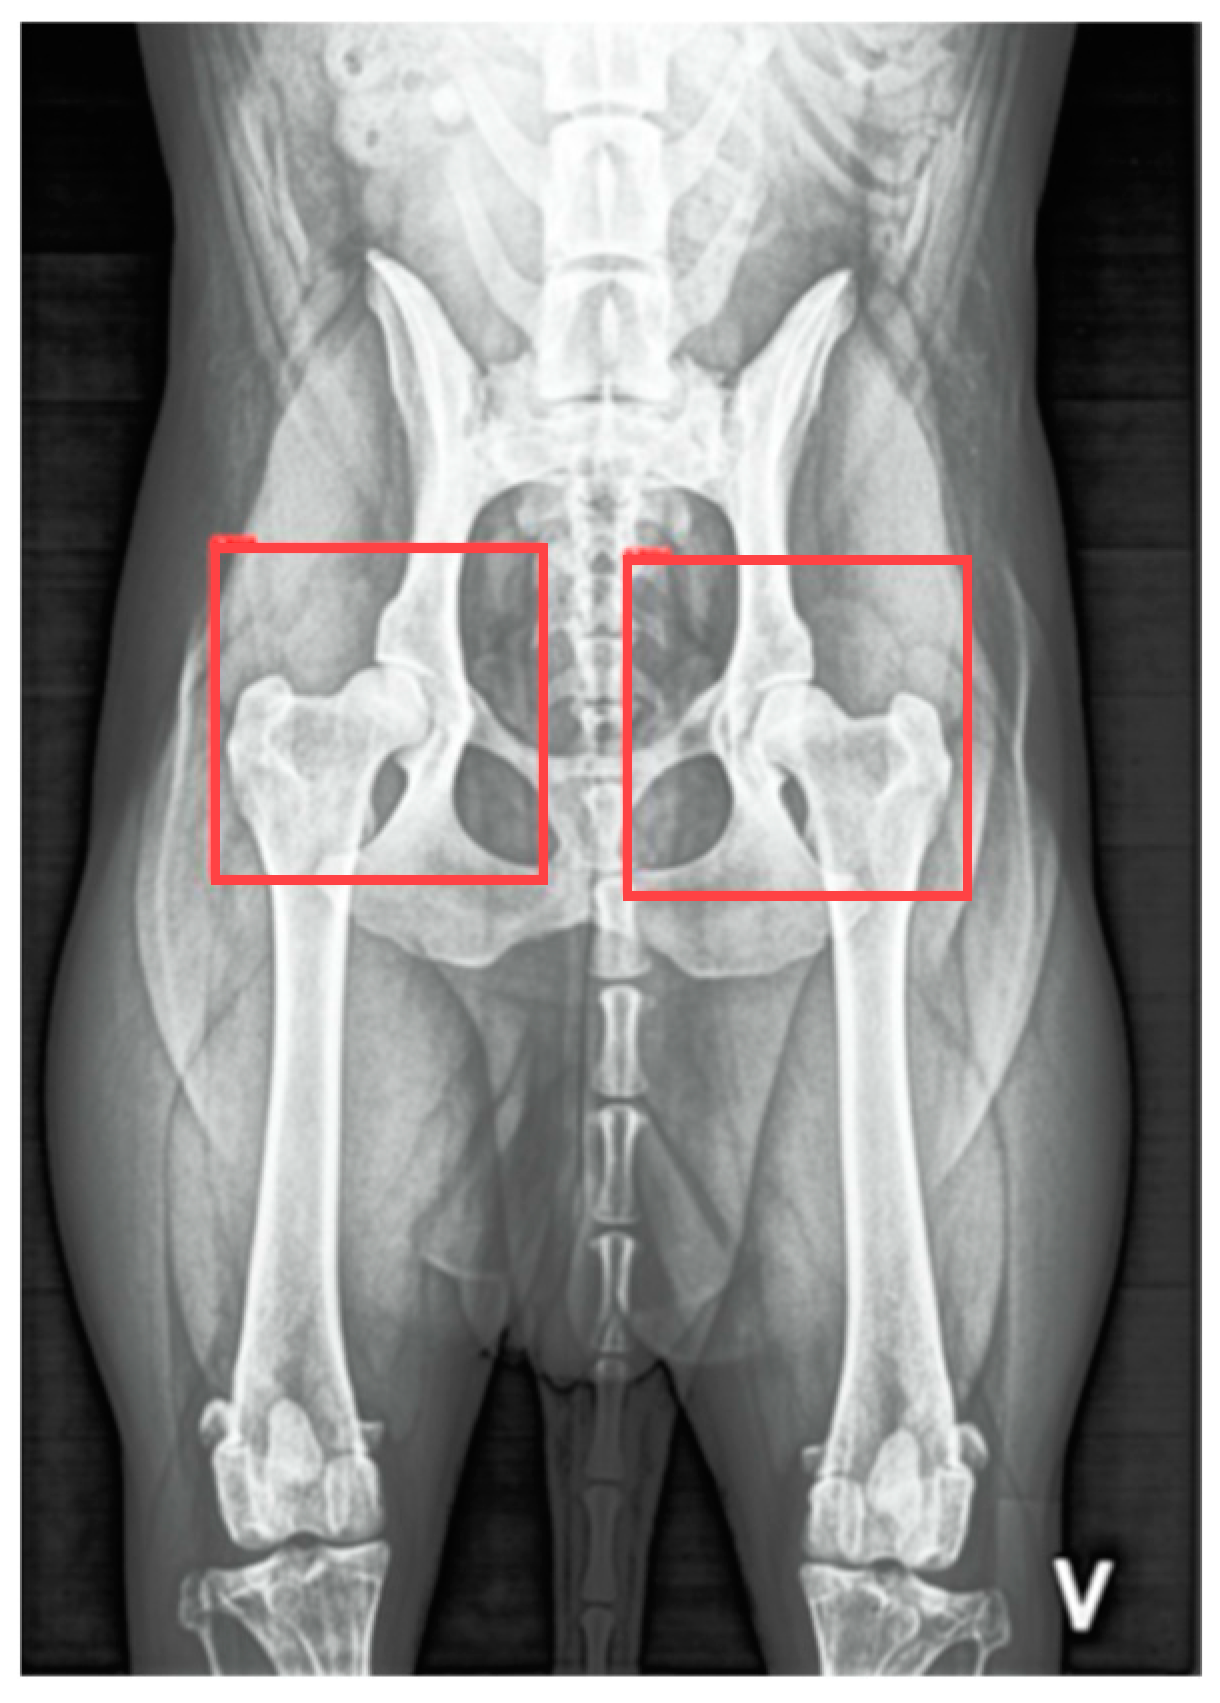

For the first dataset, 7967 annotated VDHE images from the University of Copenhagen and the Danish Kennel Club databases were used, with bounding boxes indicating the spatial locations of the hip joints (Figure 2).

Figure 2. Illustration of boundary boxes demarcating the hip joints on a ventrodorsal hip-extended (VDHE) radiographic image, representing the regions of interest.